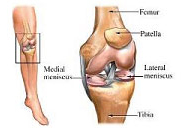

La articulación de la rodilla está formada por las partes inferior del fémur, superior de la tibia y posterior de la rótula actuando como una gran bisagra. Es la articulación más lesionada en el deportista y su tratamiento exige un gran conocimiento de la anatomía así como de la cirugía traumatológica, protésica y artroscópica.